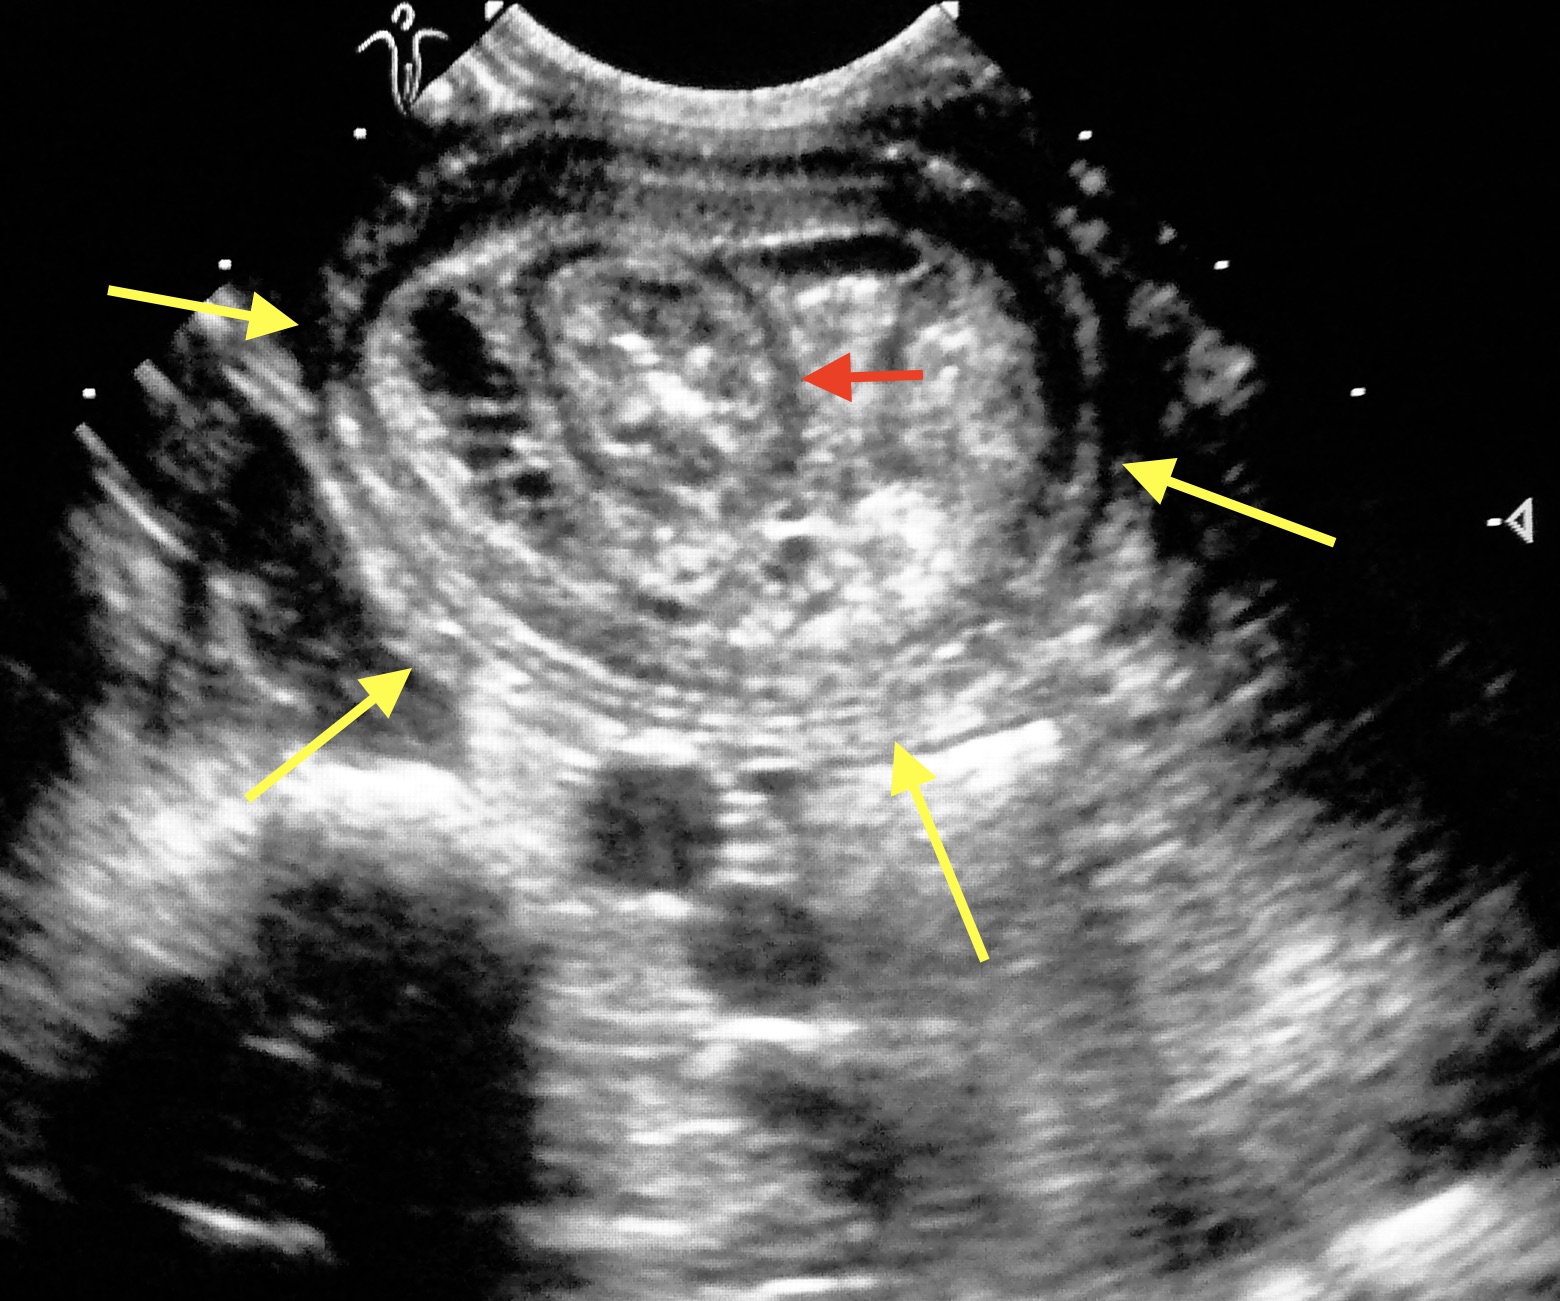

Parmi les chirurgies des tissus mous, les interventions dans l’abdomen occupent une place importante en chirurgie vétérinaire. En effet, parmi les premières interventions pratiquées, on trouve les stérilisations des chiennes et des chattes (ovariectomies), le retrait des ovaires s’accompagnant parfois du retrait de l’utérus (ovario-hystérectomie) en cas d’infection de ce dernier (métrite ou pyomètre). D’autres interventions se font également en routine : exérèse de la rate (splénectomie), le plus souvent à cause d’une tumeur ; ouverture de la vessie (cystotomie) pour retirer des calculs ; ouverture de l’intestin (entérotomie) pour en extraire un corps étranger, voire résection d’un segment d’intestin (entérectomie), par exemple en cas de tumeur, d’intussusception (l’intestin se retourne « en doigt de gant »), ou de lésion majeure et irréversible de la paroi, du fait du passage d’un corps étranger.

Et puis il y a des interventions plus spécialisées : exérèse de la vésicule biliaire (cholécystectomie), exérèse d’un ou plusieurs lobes du foie, notamment en cas de tumeur, correction d’un shunt porto-systémique (un vaisseau anormal « court-circuite » le foie), mise en place d’une dérivation (SUB) en cas d’occlusion d’un uretère par des calculs, ou encore repositionnement d’un uretère ectopique.

Notre patient est maintenant bien réveillé dans son box. Si sa chirurgie était une intervention « de convenance » (stérilisation…) ou de courte durée (petite plaie…), si son état général était bon avant l’intervention… alors la sortie se fera le soir même. De toute façon, ne sortent le soir de l’intervention que les animaux parfaitement réveillés, qui se déplacent, montrent de l’intérêt pour la nourriture, et aucun signe de douleur. En revanche, les chiens, chats ou NAC ayant subi une intervention plus lourde (ovario-hystérectomie pour retirer un utérus plein de pus, entérotomie pour extraire un corps étranger de l’intestin…), même s’ils sont bien réveillés et manifestent bruyamment leur désir de rentrer à la maison, resteront hospitalisés jusqu’au lendemain. Troisième catégorie : ceux qui sont arrivés en mauvais état, par exemple avec une péritonite, suite à une perforation de l’intestin. S’ils sont arrivés couchés sur le côté et à moitié comateux, même si le problème a été réglé chirurgicalement, et que l’état de choc et la douleur ont été pris en charge, ils ne vont pas faire des saltos arrières dès le réveil. Ceux-là resteront donc hospitalisés, à la fois pour continuer à recevoir les soins qu’ils ne pourraient recevoir à la maison, (soins de drain, mise sous oxygène…), et dans l’attente d’un retour à un état général correct, estimé à la fois d’après l’état clinique (incluant la reprise de l’appétit), et si nécessaire par des examens complémentaires (normalisation de paramètres sanguins, contrôle échographique du site chirurgical dans l’abdomen…)